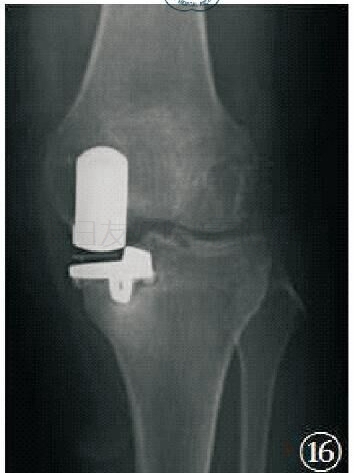

对于胫骨假体:①在前后位,假体与胫骨轴成角90°(容许5°误差)。其外侧靠近髁间嵴,内侧缘达到胫骨内侧骨皮质,并允许轻度伸出,但不要超出胫骨皮质内侧2 mm。骨—假体界面应该显示出薄层连续骨水泥层并向骨质渗透几毫米。骨水泥在外侧面及龙骨周围渗入的范围比在中间渗入的更深。②在侧位,胫骨假体需要后倾7°,即假体水平面向后下倾斜与胫骨纵轴成7°角(容许5°误差)。假体后缘应该达到后侧皮质,但悬出不超过 2 mm。若悬出过多,可能意味着胫骨假体龙骨槽开槽时损害了胫骨后侧骨皮质。

胫骨假体前后位、侧位示意图